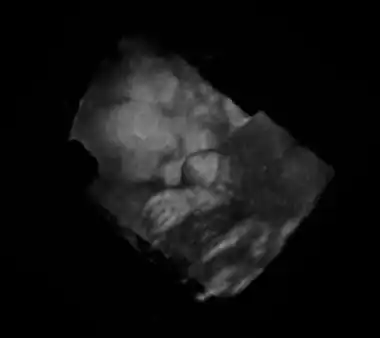

Mehrdimensionale Anwendung

Als weitere Applikation wurde in den letzten Jahren (Anfang des 21. Jahrhunderts) die dreidimensionale Echografie entwickelt. Der 3D-Ultraschall produziert räumliche Standbilder, und der 4D-Ultraschall (auch genannt Live-3D: 3D plus zeitliche Dimension) lässt dreidimensionale Darstellung in Echtzeit zu. Für ein dreidimensionales Bild wird zusätzlich zum Scan in einer Ebene ein Schwenk der Ebene vollzogen. Der Flächenscanwinkel wird gleichzeitig mit dem zweidimensionalen Bild abgespeichert. Eine weitere Möglichkeit besteht in der Verwendung einer zweidimensionalen Anordnung von Ultraschallwandlern in einem sogenannten Phased Array (siehe Ultraschallsonde), bei der nicht mechanisch, sondern elektronisch ein Schwenk des Strahles durchgeführt wird.

Die Daten werden für die Bildverarbeitung und Visualisierung von einem Rechner in eine 3D-Matrix eingetragen. So können dann Darstellungen von Schnittebenen aus beliebigen Blickwinkeln auf das Objekt erzeugt oder virtuelle Reisen durch den Körper gestaltet werden. Um Bewegungsartefakte durch die Herztätigkeit zu vermeiden, wird die Aufnahme mittels EKG gesteuert.